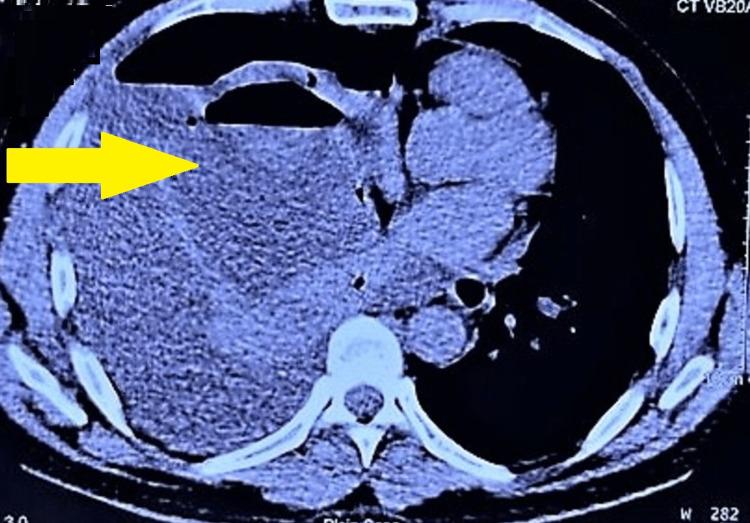

Bronchogenic cysts are closed sac-like cystic lesions resulting from abnormal budding of the primitive foregut during the early development of the alimentary and respiratory systems. We describe the case of a 54-year-old man who presented to the emergency department with complaints of fever, chills, shortness of breath, and a productive cough with intermittent hemoptysis for the past two to three months. Initial workup revealed a right lung hydropneumothorax with complete atelectasis of the right lung and a mass effect on the left lung. During intercostal drainage, pleural fluid analysis revealed empyema with treated with antibiotics. However, the symptoms persisted after five days of antibiotic treatment and drainage. A multidisciplinary team of thoracic surgeons, anesthesiologists, and pulmonologists was assembled due to the non-resolving nature of the lung abscess. The patient underwent a right middle lobe lobectomy with decortication via open thoracotomy, and a bronchogenic cyst, an uncommon cause of the lung abscess, was suggested by histopathological analysis.

支气管源性囊肿是一种封闭的囊状囊性病变,由消化道和呼吸系统早期发育过程中原发性前肠的异常芽生引起。我们描述了一名54岁男性的病例,他因过去两到三个月出现发热、寒战、呼吸急促以及伴有间歇性咯血的咳痰症状而到急诊科就诊。初步检查发现右侧液气胸伴右肺完全肺不张,且对左肺有占位效应。在肋间引流期间,胸腔积液分析显示为脓胸,给予抗生素治疗。然而,抗生素治疗和引流五天后症状仍持续。由于肺脓肿的病情未得到缓解,组建了由胸外科医生、麻醉师和肺科医生组成的多学科团队。患者通过开胸手术接受了右中叶肺叶切除加纤维板剥脱术,组织病理学分析提示为支气管源性囊肿,这是肺脓肿的一种罕见病因。